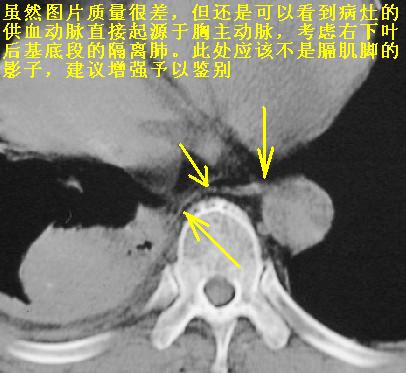

以下是引用天南地北在2007-1-24 18:00:00的发言:[br]1:右下肺内基底段类椭圆性肿快影:考虑1:右下球形肺炎2:右下肺隔离症,建议抗炎治疗后复查。[br]2:右肺及左下肺感染,右侧少量胸腔积液。